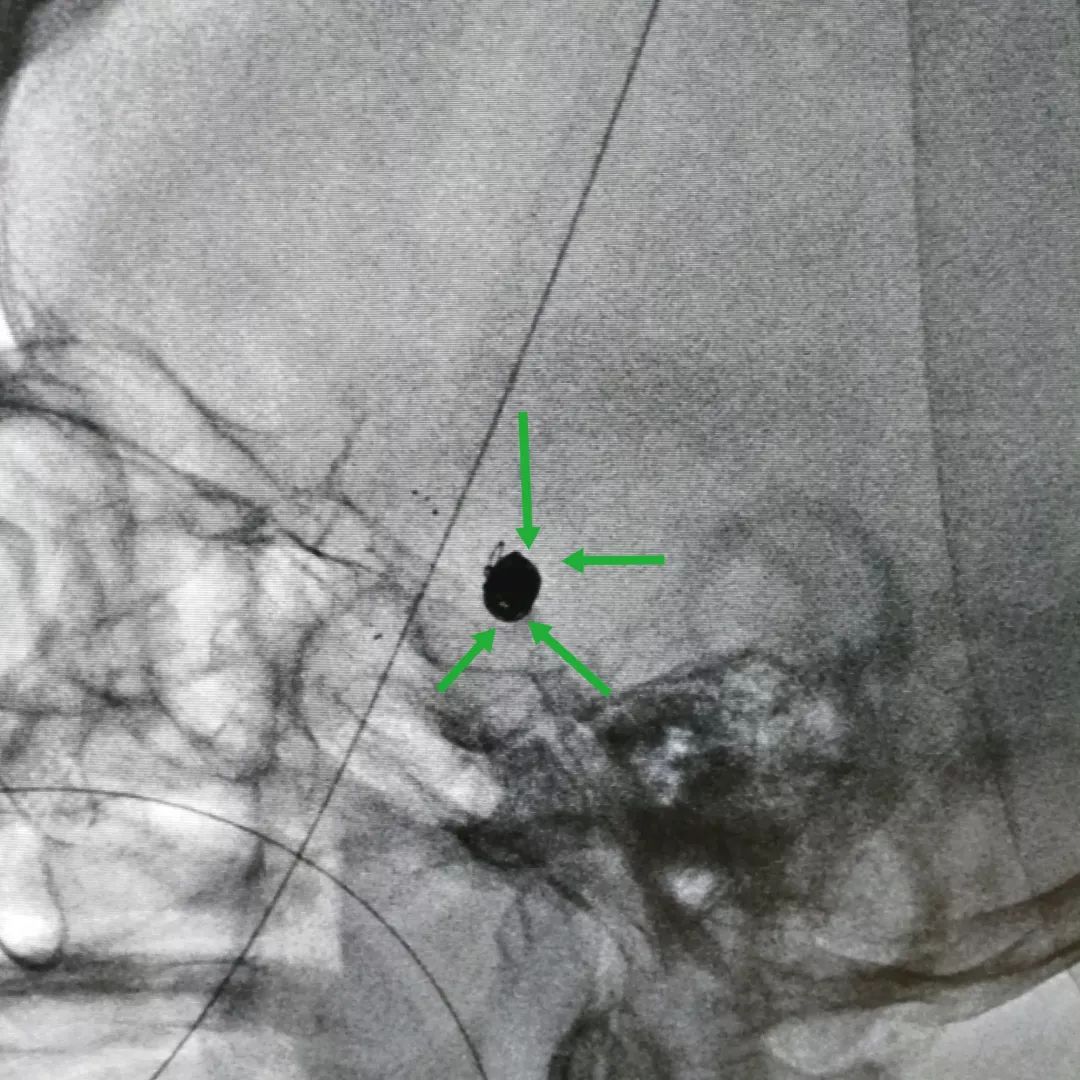

图一:脑血管造影三维重建提示左侧后交通动脉瘤,瘤颈很宽,达6.5mm,动脉瘤大小约7×8.2mm。(绿箭头为动脉瘤,红箭头为合并存在的血管狭窄)